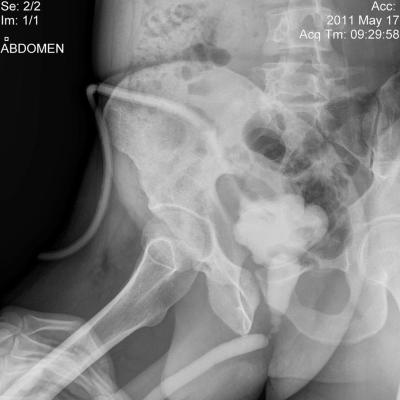

Здравствуйте! Мужу недавно сделали цистостомию, поставили диагноз: стриктура уретры (стриктура бульбозного отдела уретры около 2х см.)Стоит вопрос о "Открытой реконструктивной операции на уретре" у нас в г. Барнауле либо в Москве. Скажите пожалуйста какова вероятность успеха данной операции и как долго нужно будет находиться под наблюдением врачей, так же интересует возможно ли иное лечение при данном течении заболевания. Лечащий врач советует делать операцию в Москве, подскажите пожалуйста возможна ли бесплатная опреация, т.к. муж основной кормилец в семье, у него трое иждевенцев, я и двое детей 1 и 3 лет, наш семейный бюджет просто не потянет такую сумму. Прикрепляю фото последней уретрографии и выписку из поликлиники с точным диагнозом. Заранее большое спасибо!